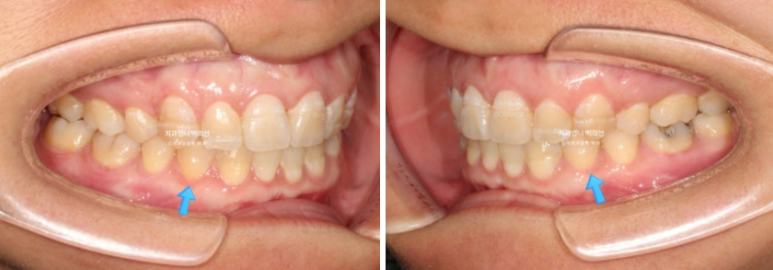

24.07

치료시작 10개월째 모습입니다.

상악 발치공간이 보입니다.

아래는 송곳니를 앞니자리로 끌어오는 중입니다.

어금니 교합관계는 정확히 1급입니다. 송곳니 자리에 있는 파란 화살표는 사실 송곳니가 아니라 첫번째 작은어금니입니다.